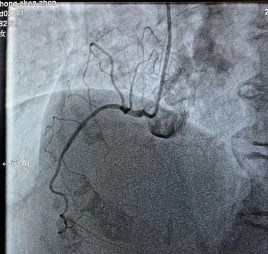

右冠脉细小,未见明显狭窄